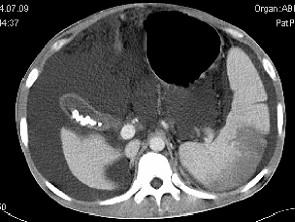

问题 患者男,29岁,乙肝病史10余年,腹胀,有移动性浊音,影像检查如图,最全面的诊断是 ( )

选项 A、大网膜膈下间位及脾梗 B、胆结石及脾梗 C、肝硬化腹水 D、肝硬化腹水、脾梗、胆囊结石 E、肝硬化

答案 D